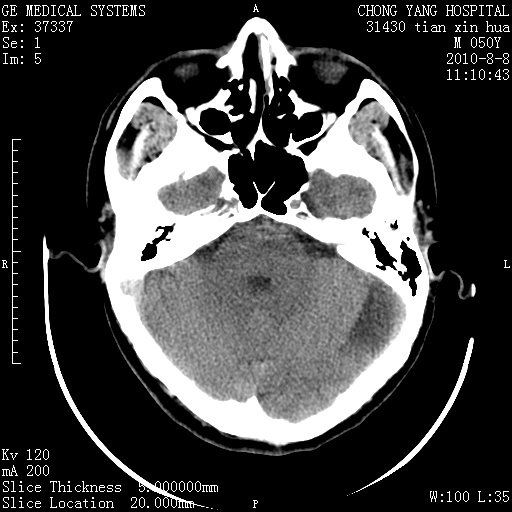

标题: CT28268:M50Y 头部外伤。 [打印本页]

标题: CT28268:M50Y 头部外伤。

考虑左侧枕部硬膜下积液。

乙状窦增宽,蛛网膜囊肿不除外

考虑左侧枕部蛛网膜囊肿;建议行mri检查。

病灶两端有脑膜尾征,考虑蛛网膜囊肿

枕骨稍变薄,脑组织有受压。首先考虑蛛网膜囊肿。